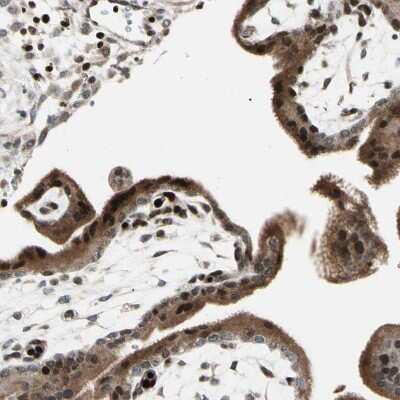

Immunohistochemistry-Paraffin: IHPK2 Antibody [NBP1-89635] - Staining of human placenta shows strong nuclear positivity in trophoblastic cells.